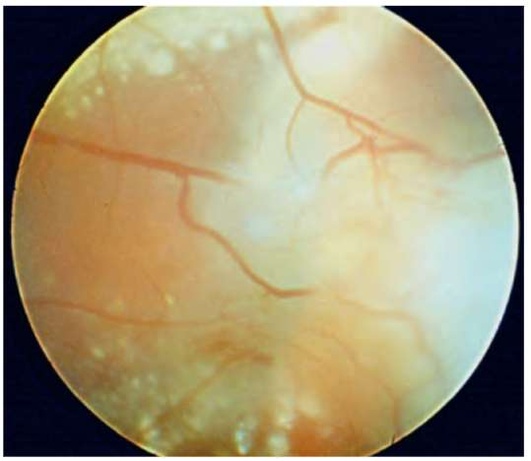

Рис. 23.1. Оптический неврит при рассеянном склерозе